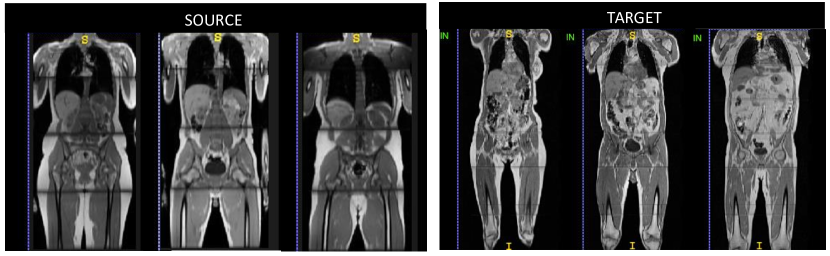

Source domain (S): The dataset is obtained from our MALIBO study (MAchine Learning In whole Body Oncology) and includes abdominal T1-weighted MR Dixon images of 35 healthy subjects. We consider this dataset as the source domain used to train the initial classifier in a supervised manner as manual organ annotations are available for all subjects. The images have size of and resolution mm.

Target domain (T): Data for the target domain is obtained from the UK Biobank (Application 12579). We use 45 subjects with manually annotated T1-weighted Dixon MR images which have been acquired with a similar protocol as the MALIBO data. The main obvious differences are the image size and resolution mm.

Source and target dataset are acquired at different centers. UK Biobank data is acquired with a Siemens 1.5T MAGNETOM Aera scanner while in MALIBO a Siemens 1.5T MAGNETOM Avanto was used. For our study, we use the T1-weighted in-phase images from the Dixon protocol. We focus on organ segmentation within whole-body scans. As a pre-processing, image intensities in both datasets are normalized to zero-mean and unit-variance. Images are resampled to the same size and physical resolution. Visual examples from the source and target database are depicted in Figure 1. Despite the similarity of the scanning protocol and same scanner manufacturer, the drop in segmentation accuracy when applying a model trained on MALIBO and tested on UK Biobank data is striking, as we will show in our experiments. The images seem to encode a significant bias in their appearance which is not obvious upon visual inspection.